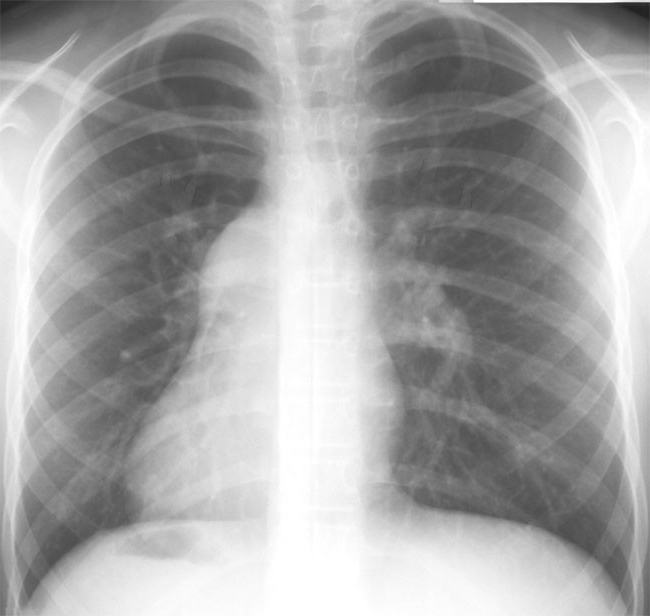

- Рентгенологическое исследование органов грудной полости. Помогает оценить состояние органа и выявить любые нарушения в легких.